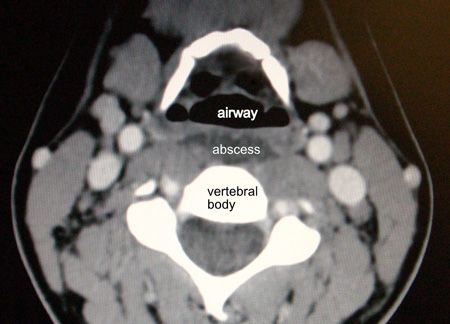

A CT scan of the neck (Figure 3) confirmed the diagnosis and helped determine whether surgery would be needed.

Figure 3

Diagnosis. A lateral neck x-ray film is 85% to 90% sensitive for retropharyngeal abscess. CT scanning is more sensitive, especially in children, where x-ray films can be falsely positive, and can help determine whether surgery is necessary and, if so, by what approach. CT does, however, expose the patient to high radiation dosage and may be avoided in milder cases that respond clinically to medical therapy, especially in younger patients in whom risks of radiation are higher. In this patient, CT images note the dark fluid collection anterior to the vertebral body.